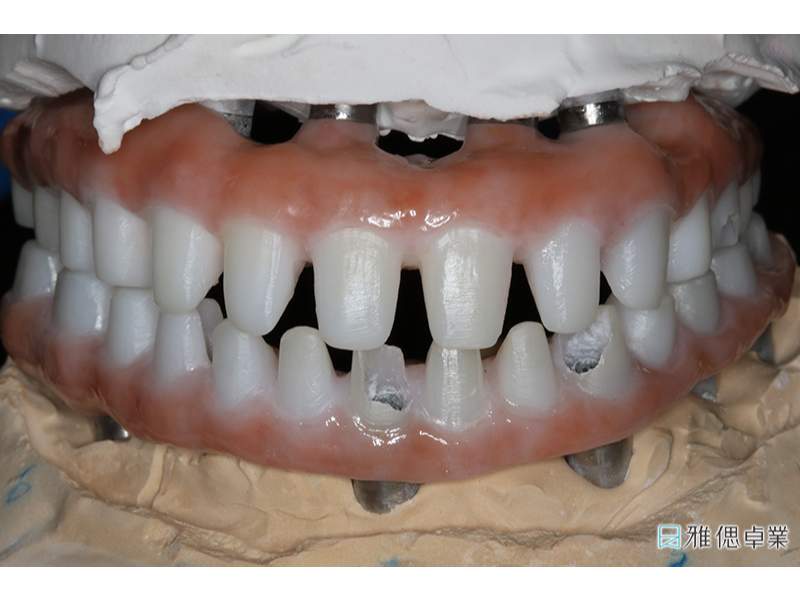

全口假牙模型,模擬自然牙支台齒

假牙模型上顎

假牙模型下顎